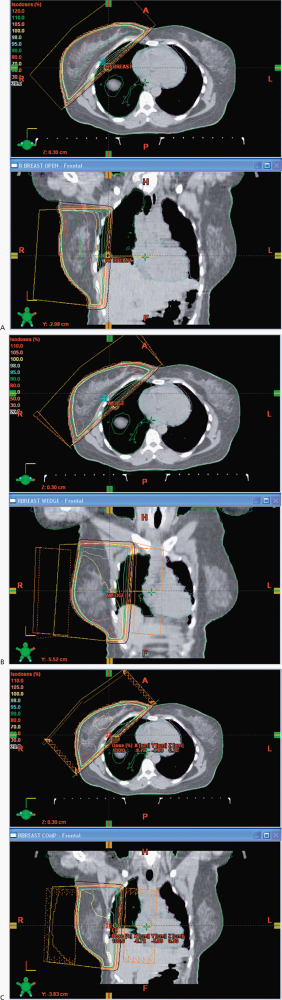

In this case, I would propose a boost of 10 Gy for a total dose of 60 Gy. The primary fields for the whole breast are opposed tangents with the patient on a breast board to obtain good geometry for breast coverage with the arms over the head in a supine position. We use a vac-loc to immobilize the head, arms and upper torso on the breast board with the board elevated to bring the mid sternum parallel to the couch and posterior collimator. We try to avoid, if possible collimator rotations to minimize beam divergence, and half beam block the deep portion of the tangent. The breast is outlined with wires placed at the superior, medial, inferior and lateral borders. The anatomic landmarks include the inferior margin of the head of the clavicle, mid sternum, 2 cm below the inframammary fold and the mid-axilla line. As all chest/breast setups are clinical, we do a control scan in the mid-region of the breast to identify the positioning and verify correctness of the lateral wire, which often requires some adjustment. This will minimize the setup uncertainty. The images are then sent to the treatment planning system for block design, with blocks placed to insure coverage of the breast tissue while minimizing the dose to the lung, heart, contralateral breast, and accounting for breathing motions. Some centers use deep inspiration breath hold technique, but this requires a fast scanner and rapid treatment administration. The boost field is generally given with electrons and if electrons are not suitable due to depth then a reduced opposed tangent field is useful. We do not treat the axilla.

The ACR categorization is consistent with my own recommendations: Treat the whole breast to 50 Gy at 2 Gy/fraction using opposed tangents then boost with a direct electron field an additional 5 fractions at 2 Gy/fraction to the lumpectomy cavity + 2 cm margin for a total dose of 60 Gy to the cavity.

The whole breast should be treated to 50 Gy at 2 Gy/fraction. Alternatively, the breast has been treated to 46-50.4 Gy at 1.8 Gy/fraction. While there are studies that do not show benefit to boost, the ACR recommends a boost, although with a less score than for whole breast radiation. Most radiation oncologists recommend boost per the ACR appropriateness criteria, although they are somewhat wishy washy. Her risk factors are close margins, however, that has been cleared by the re-excision. The margins are negative. I would boost 10 Gy at 2 Gy/fraction to 60 Gy to the lumpectomy cavity.

She should receive radiation to the whole breast using opposed tangents, 6 MV, followed by a cavity boost to 60 Gy. The whole breast dose is 50 Gy at 2 Gy/fraction. The boost is reasonable in younger women with higher grade tumors.